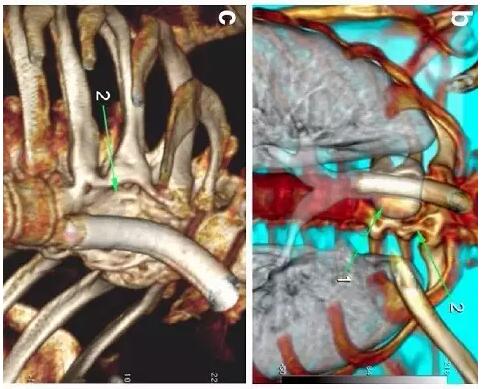

胸部CT顯示氣切套管氣囊周圍氣管擴張,胸1-4椎體前部受到侵蝕(下圖a-c)。

下圖箭頭1為氣切套管氣囊緊貼T1-4椎體水平,造成椎體前部受到侵蝕(箭頭2):